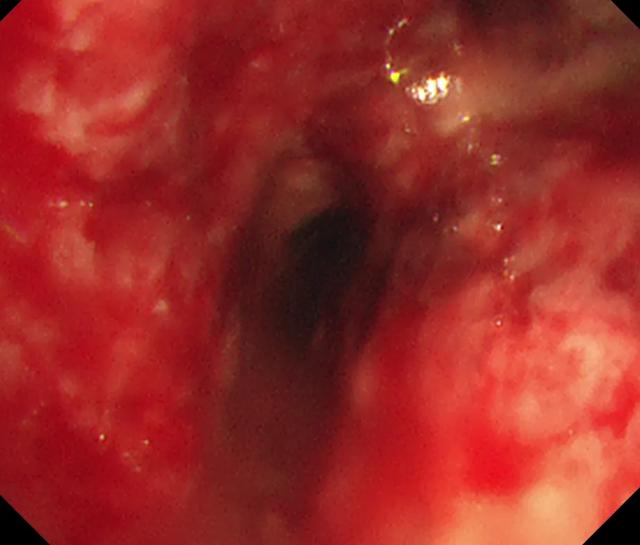

病因二:结核,真菌感染(组织胞浆菌、隐球菌)等感染性原因也是良性气道狭窄的重要原因,特别是结核是我国最常见的原因。以下列举两例不同表现的气管支气管结核患者。病例3,女,24岁,因II型呼衰神志不清送入急诊抢救,普通气管插管无法插入,仅能插入5号气管插管通气,气管插管后病情反而急剧加重,超细支气管镜见气管完全被坏死物堵塞,考虑气管支气管结核(溃疡坏死型),紧急ECMO下清理坏死组织,通畅气道后撤机,抗结核治疗后完全康复。病例4,女,41岁,气管支气管结核,疤痕狭窄型,左主支气管及左上叶支气管疤痕狭窄,反复球囊扩张6次好转。

图:病例3 气管黏膜糜烂坏死、病例4 患者左主支气管疤痕狭窄